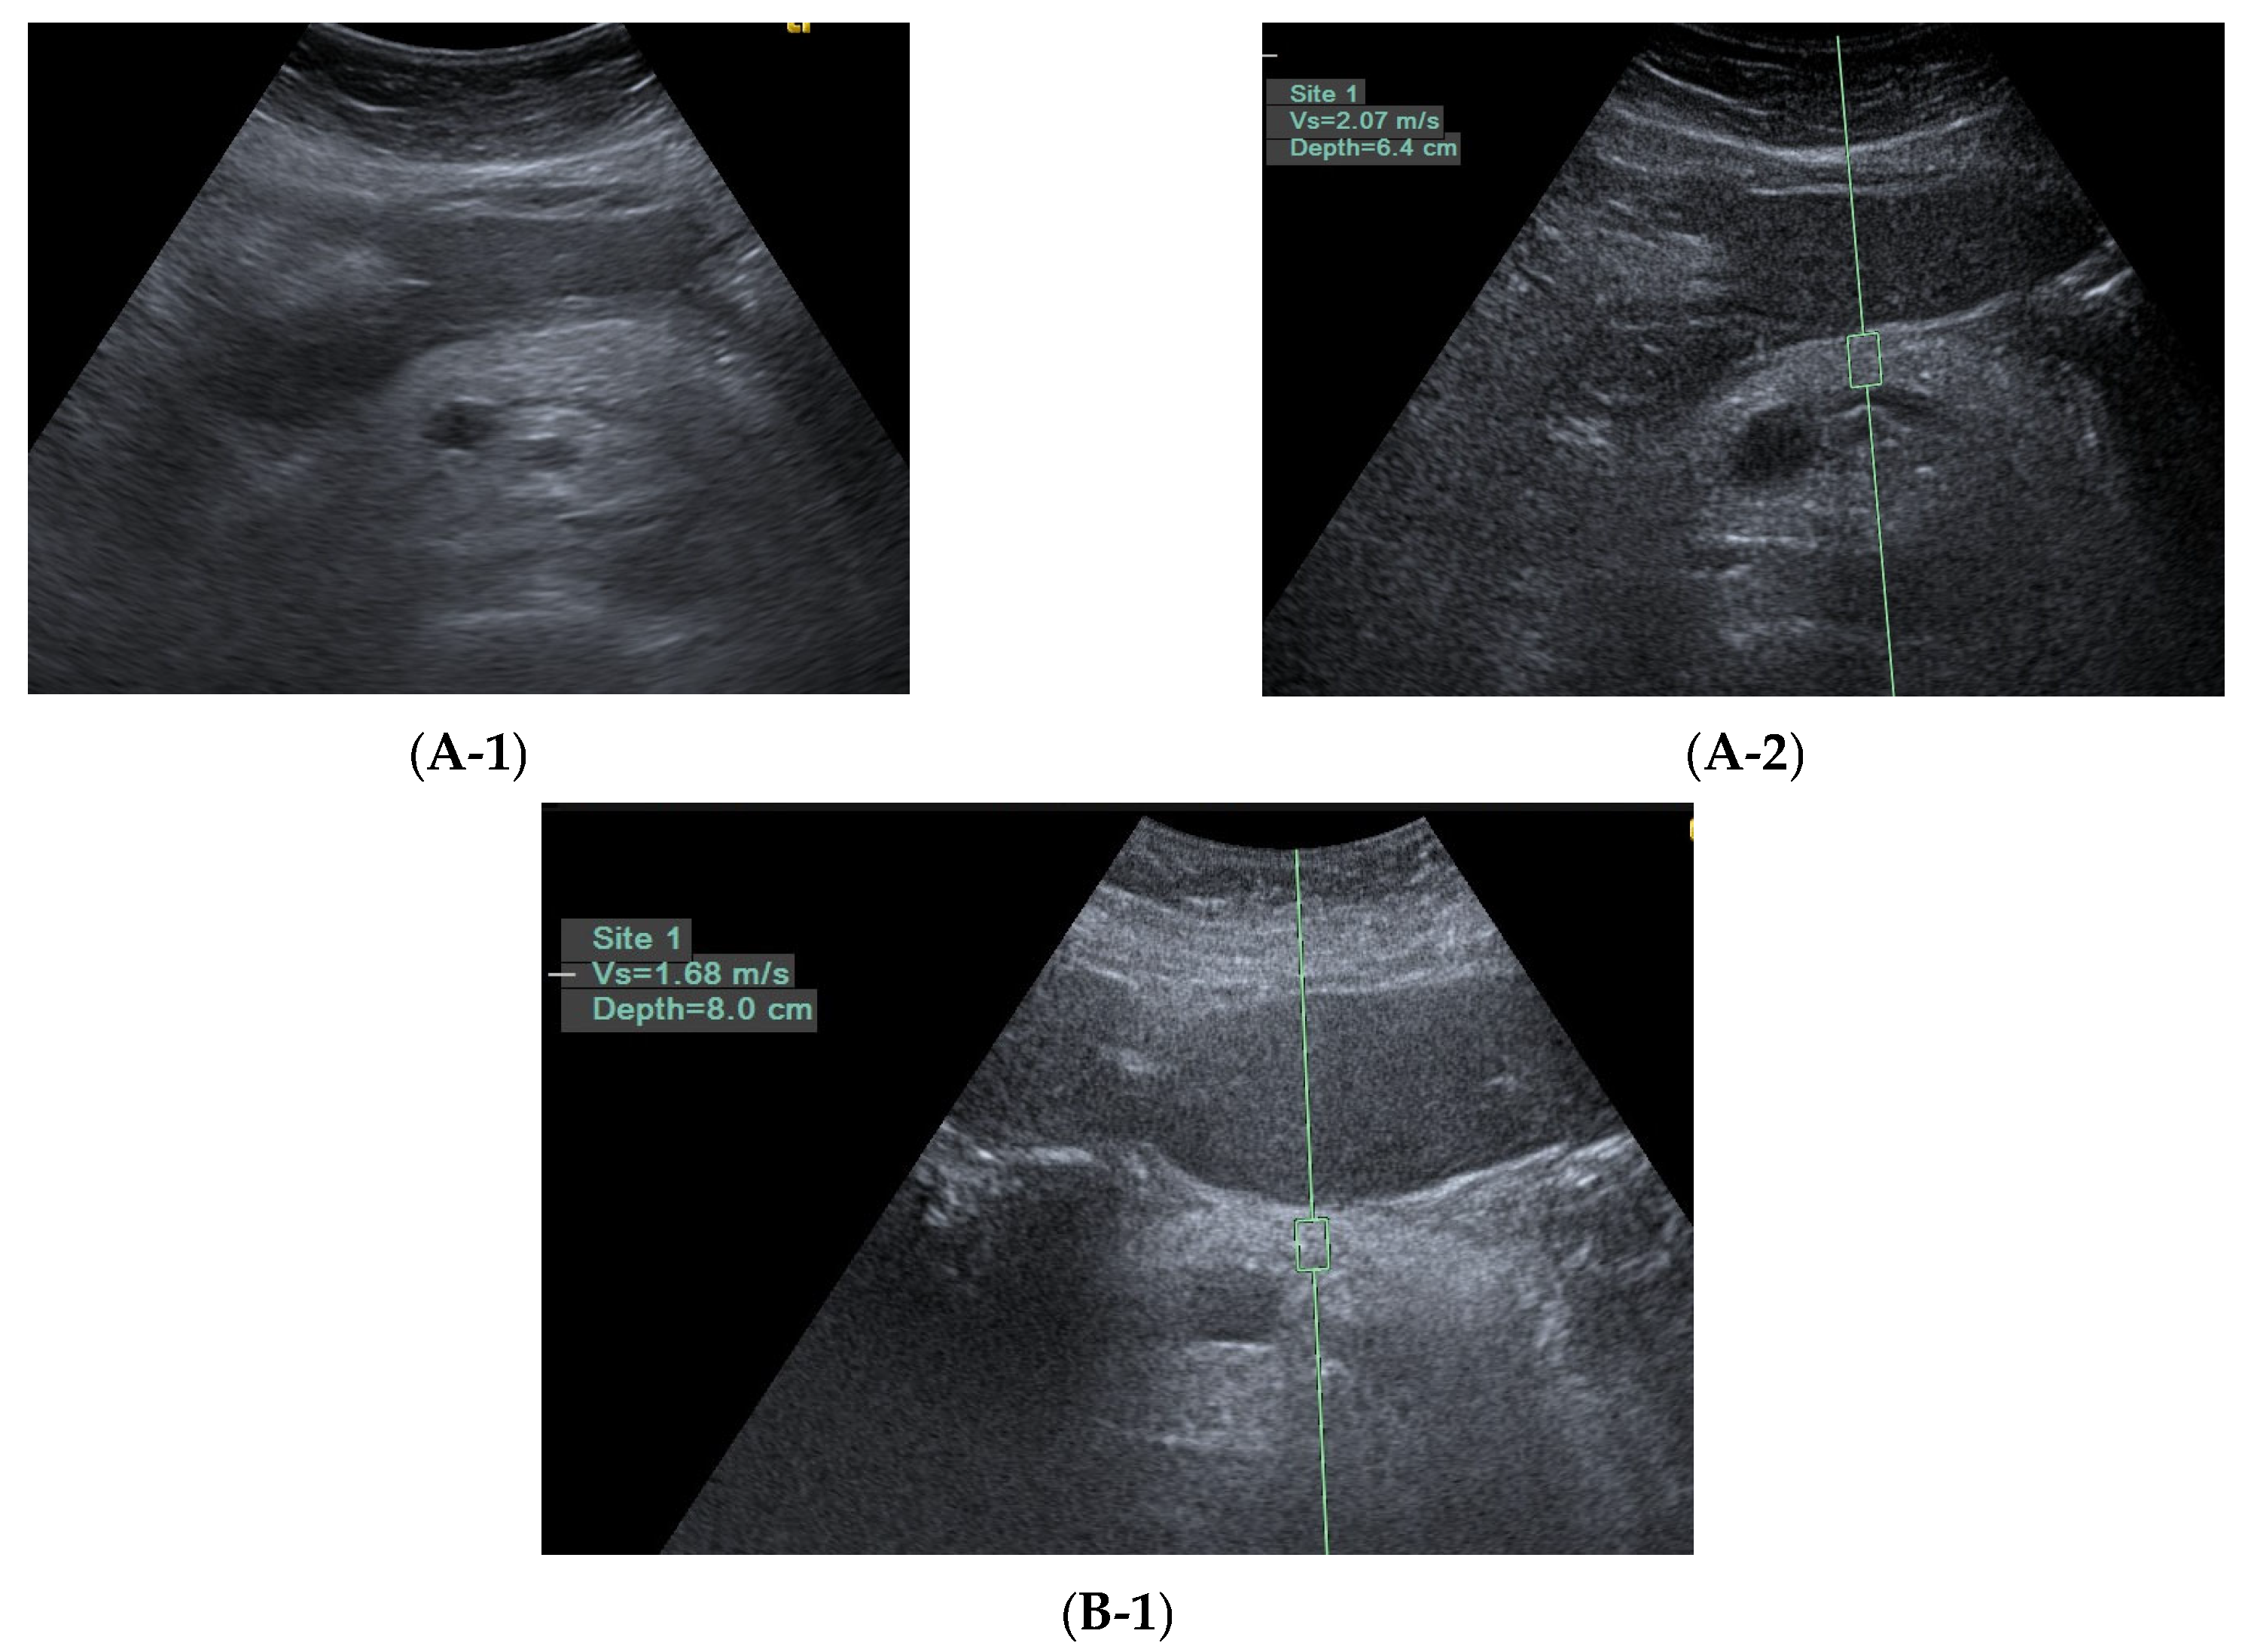

- Huang, C.-T.; Lee, T.-H.; Lin, C.-K.; Chen, C.-Y.; Yang, Y.-F.; Liang, Y.-J. Pancreatic Fibrosis (Early Chronic Pancreatitis) as Emerging Diagnosis in Structural Causes of Dyspepsia: Evidence from Endoscopic Ultrasonography and Shear Wave Elastography. Diagnostics 2021, 11, 1252. [Google Scholar] [CrossRef]

- Huang, C.T.; Lin, C.K.; Lee, T.H.; Liang, Y.J. Pancreatic Fibrosis and Chronic Pancreatitis: Mini-Review of Non-Histologic Diagnosis for Clinical Applications. Diagnostics 2020, 10, 87. [Google Scholar] [CrossRef]

- Hristov, B.; Andonov, V.; Doykov, D.; Tsvetkova, S.; Doykova, K.; Doykov, M. Evaluation of Ultrasound-Based Point Shear Wave Elastography for Differential Diagnosis of Pancreatic Diseases. Diagnostics 2022, 12, 841. [Google Scholar] [CrossRef]

- Wekerle, M.; Murillo, K.; vonBoscamp, M.; Hauber, V.; Ebert, M.P.; Antoni, C.; Hirth, M. Point-shear wave elastography generated by acoustic radiation force impulse in chronic pancreatitis. United Eur. Gastroenterol. J. 2024, 12, 667–677. [Google Scholar]

- Shintani, S.; Inatomi, O.; Okamoto, T.; Hiroe, K.; Eguchi, T.; Tomozawa, Y.; Inoue, A.; Kimura, H.; Nishida, A.; Tsuji, Y.; et al. Diagnostic accuracy of endoscopic ultrasonographic shear wave elastography for assessing early chronic pancreatitis using the Japanese diagnostic criteria 2019. DEN Open 2025, 5, e387. [Google Scholar] [CrossRef]